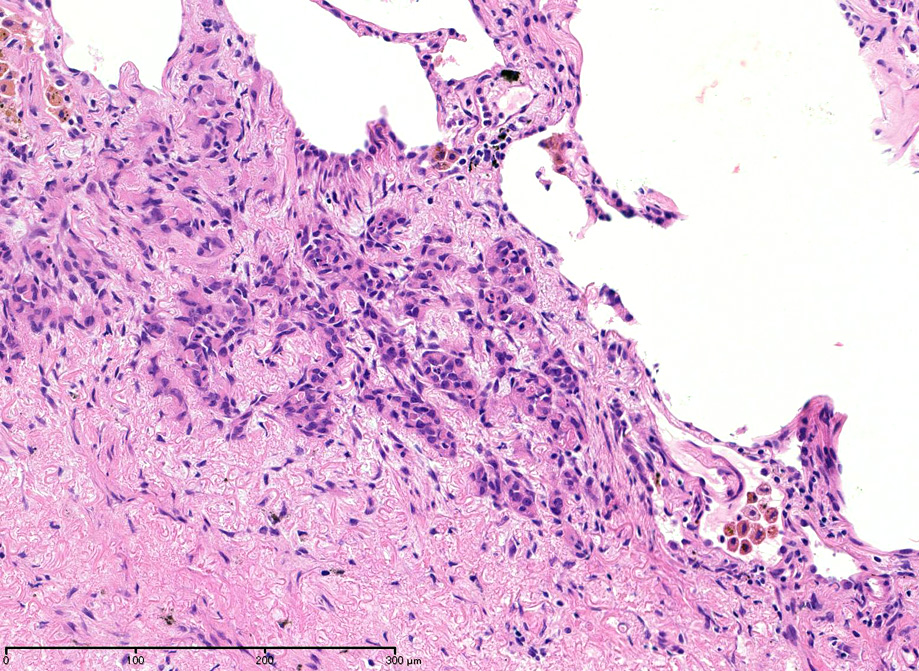

直径5-6mmの, 中央に弾性線維をふくむfibrous noduleがあり, 腫瘍細胞は結節の辺縁部に沿って認められる。

hyperchromaticな類円ないし多角の核で好酸性の広めの細胞質をもつ上皮様細胞が増殖している。右図では血管内を占拠するように腫瘍細胞が認められる。

左図:腺腔様の裂隙が胞巣内にみられ, 凍結標本だと腺癌との区別がむずかしい。

右図:多型細胞や異型細胞が出現。核分裂像も異常に見える。